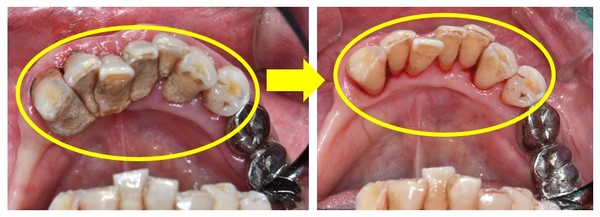

스케일링은 치아우식이나 치주질환 등 각종 구강질환의 원인이 되는 치태와 치석을 제거해 예방·관리하는 방법이다. 특히 치아에 붙어있는 치석은 칫솔질만으로는 제거되지 않기 때문에 정기적인 스케일링 치료를 통해 구강질환을 예방하는 것이 중요하다.

연 1회 건강보험 적용 기준 기간은 매년 1월 1일에서 12월 31일까지이다. 단, 잇몸치료 전 단계로 시행하는 스케일링은 치료받은 날짜를 기준으로 6개월에 1회 적용된다.